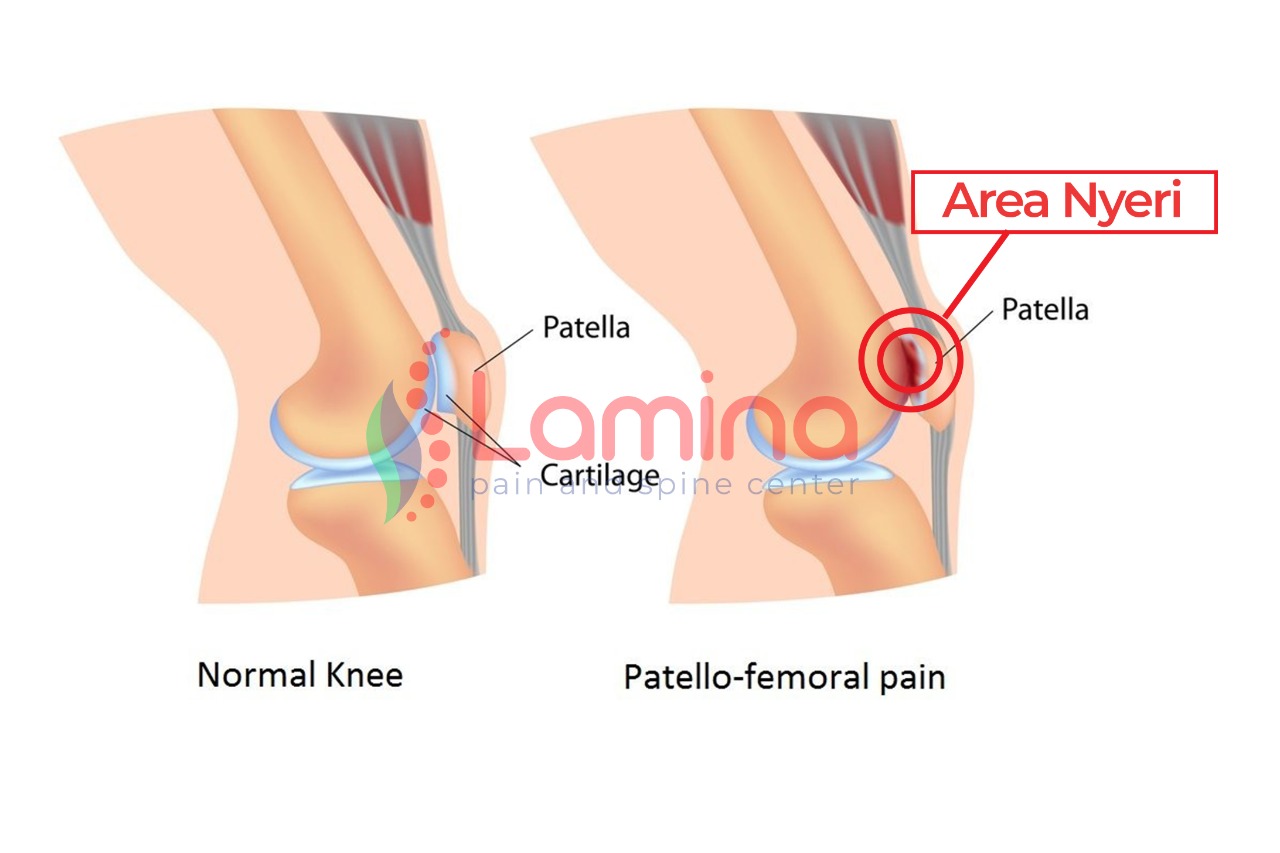

RUNNER’S KNEE (PATELLOFEMORAL PAIN SYNDROME). Sindrom Nyeri Lutut pada Pelari

Sindrom Nyeri Tempurung Lutut, Penyebab Rasa Nyeri Berkepanjangan

Bikin Lutut Nyeri, Kenali Fakta Penyakit Patellofemoral Pain Syndrome